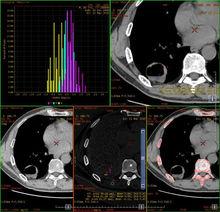

能譜曲線

能譜曲線是物質或結構的衰減(即CT值)隨X射線能量變化的曲線,從能譜曲線上可以得到40~140keV每個能量點的平均CT值和標準差。能譜曲線反應了物質的能量衰減特性,從物理學角度看,每一種物質都有其特有的能譜曲線,由此可以推斷出醫學上不同的能譜曲線代表不同的結構和病理類型,在一個有限的疾病分型中,類似的能譜曲線提示同樣或類似的結構和病理類型。能譜曲線的套用可推廣到腫瘤來源的鑑別、良惡性腫瘤的鑑別、惡性腫瘤的分級等方面。

圖9 根據能譜曲線,提示腫瘤內部為脂肪結構,診斷為肝臟血管纖維脂肪瘤(圖像來源:陝西中醫學院附屬醫院)